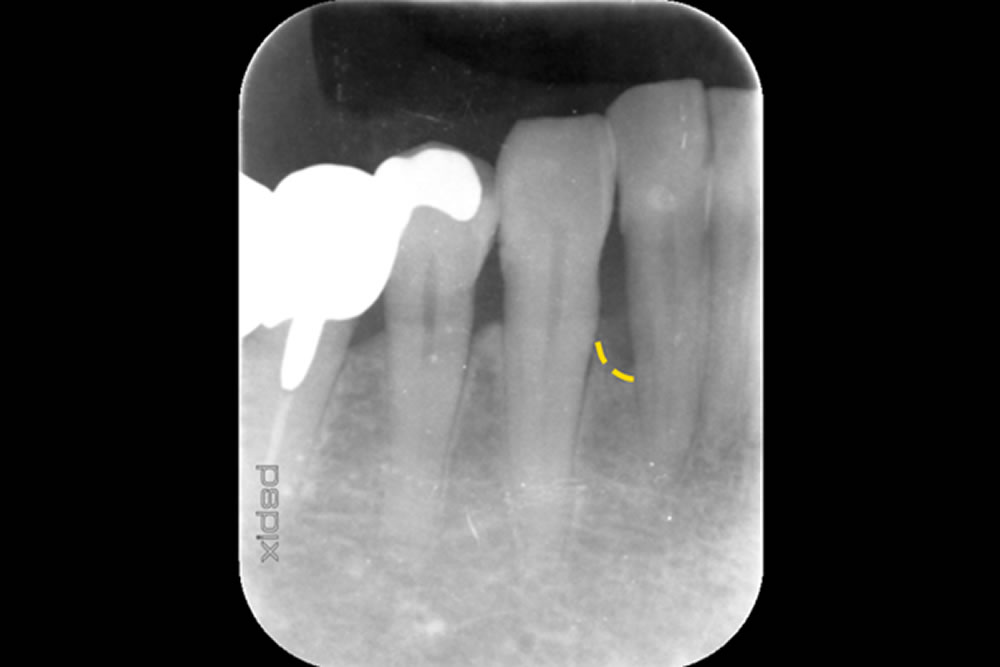

| 治療内容 | ・MIST(最小侵襲手術):できるだけ傷を小さくして回復を早める手術方法。 ・マイクロスコープ(顕微鏡)による精密歯周病治療。 ・Er:YAGレーザーで徹底的に清掃:歯根面から歯周病の原因となる「プラーク」を除去する治療。 |